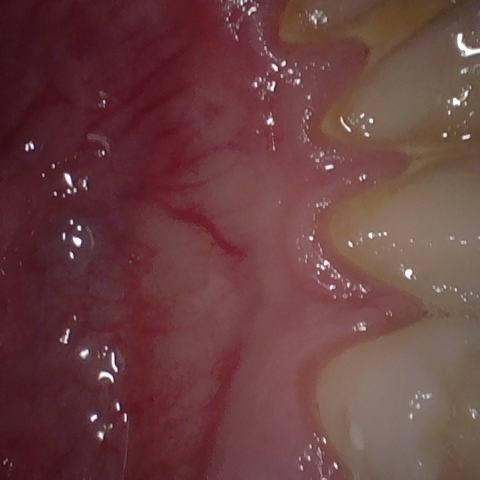

Annotated as "Good"

Original Image Rendering Image